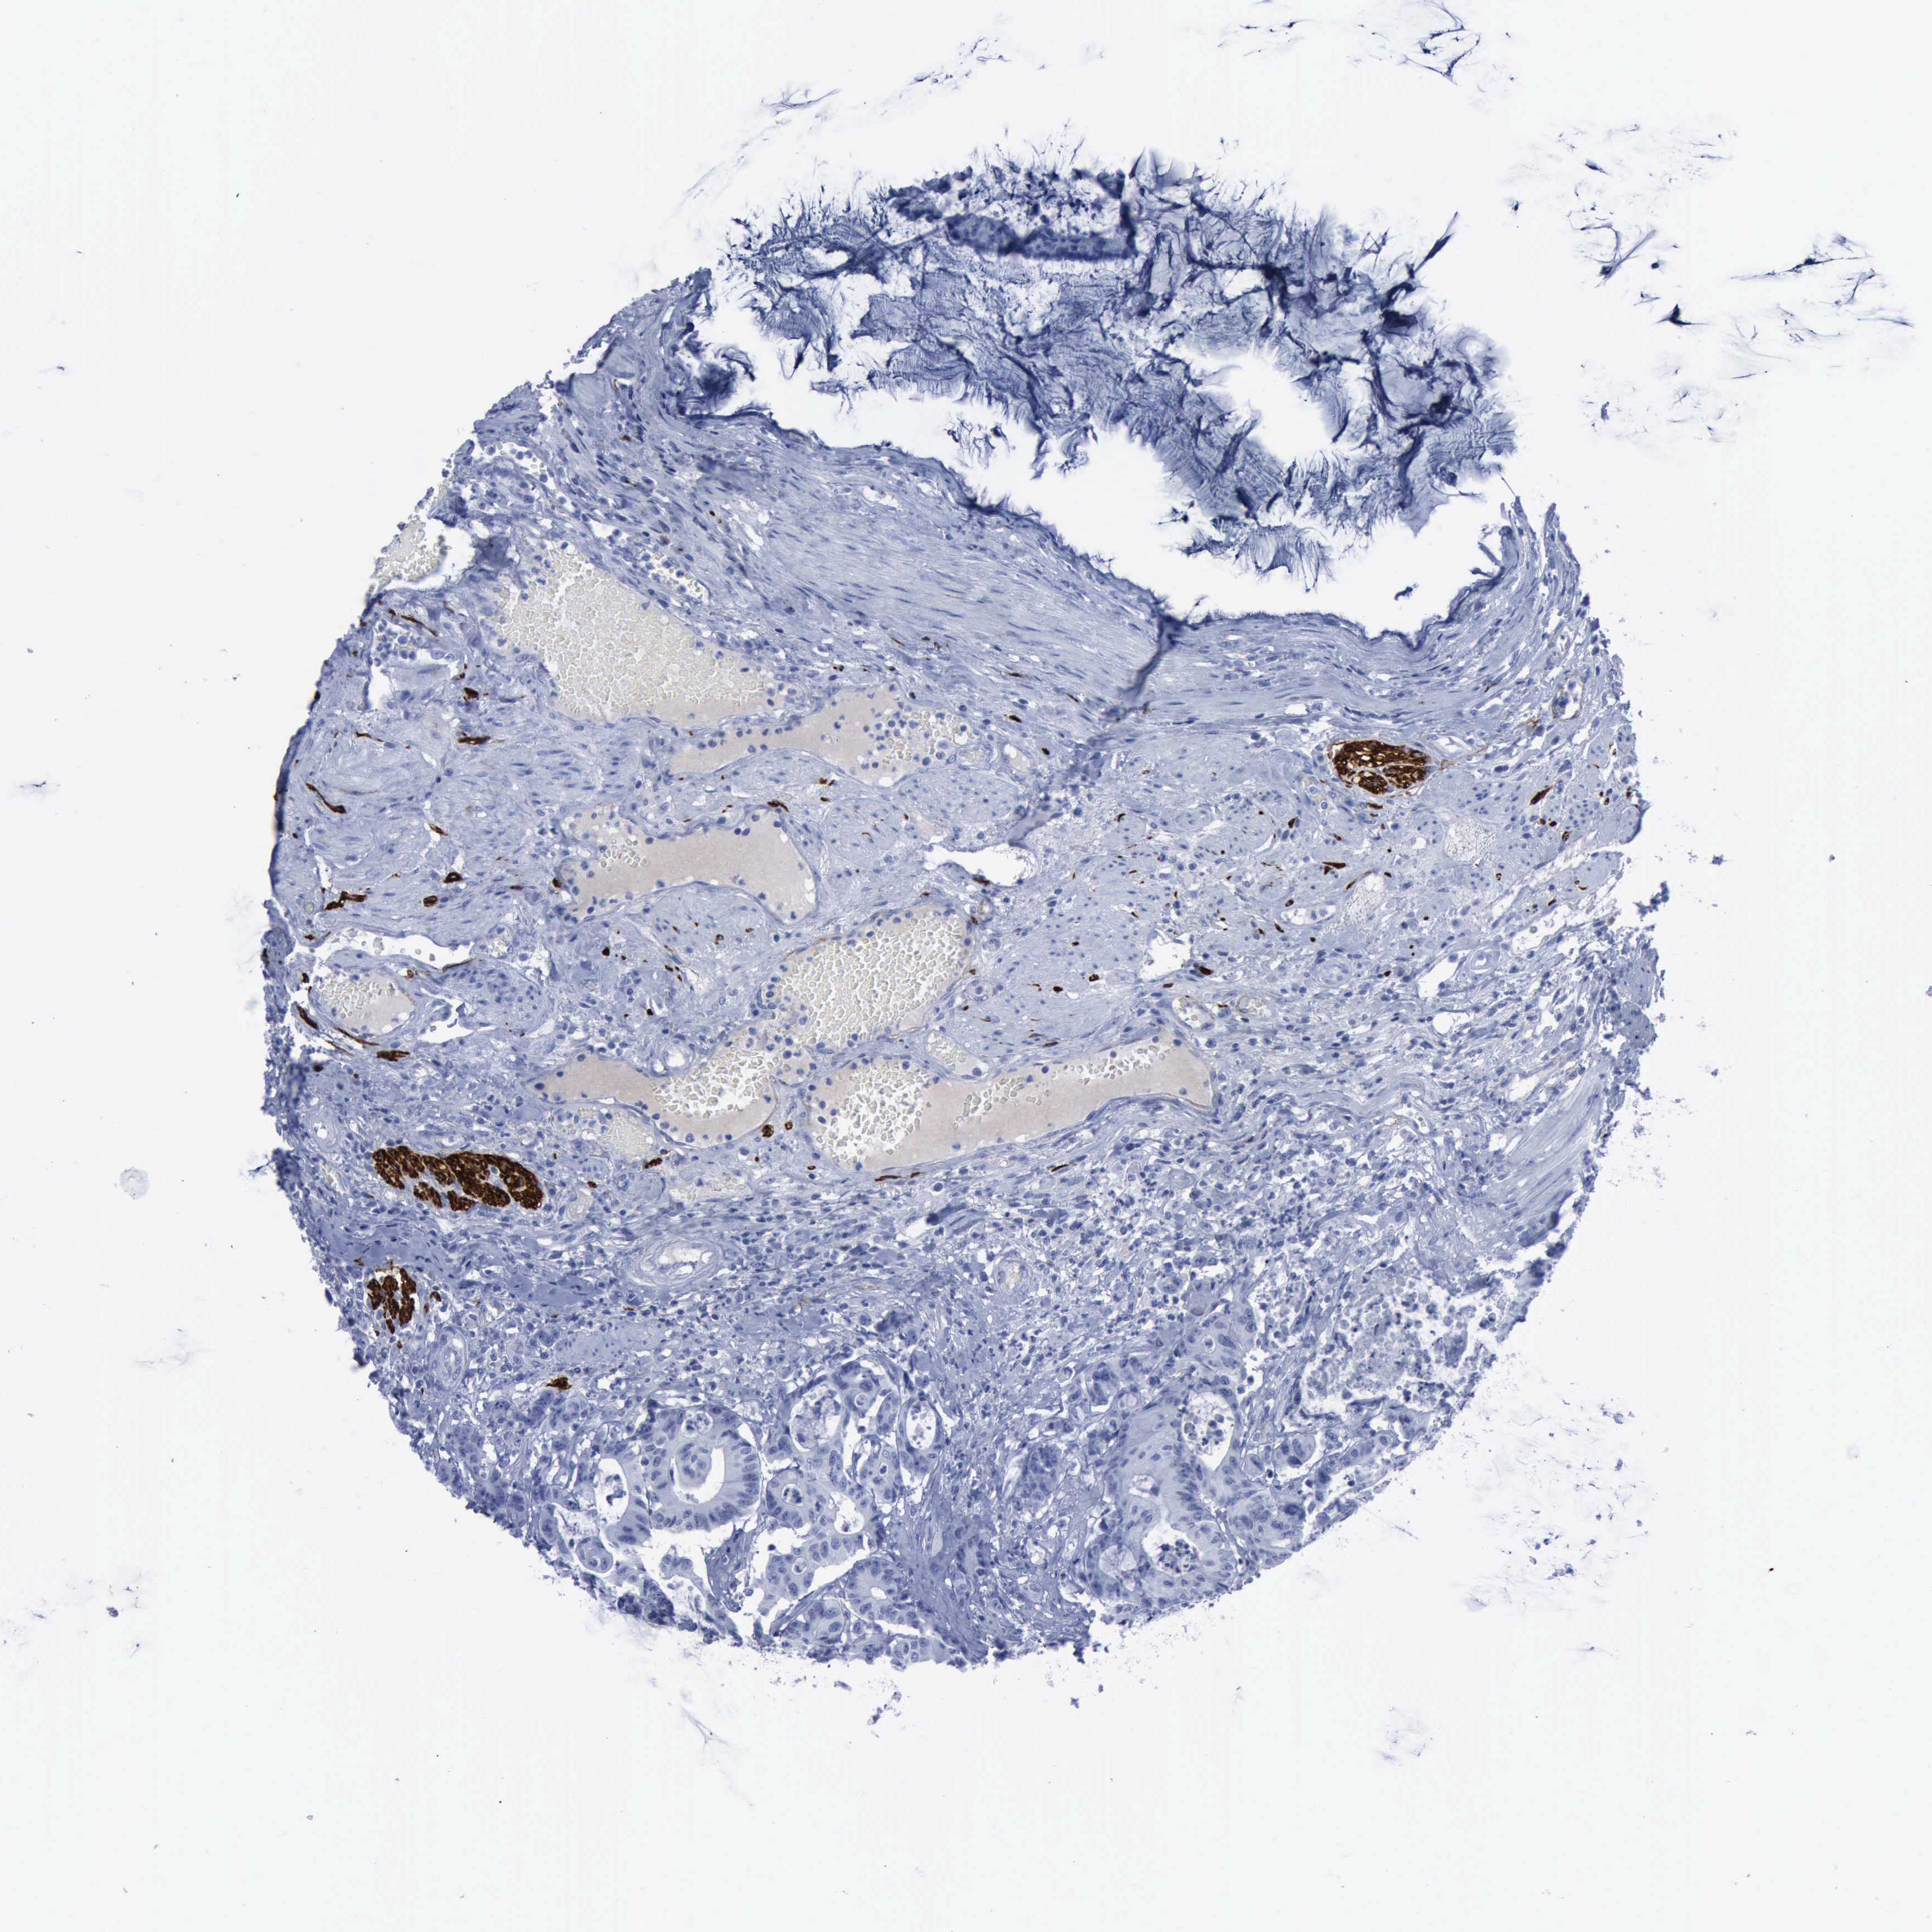

Colorectal cancer

Human cancer

Colon adenocarcinoma